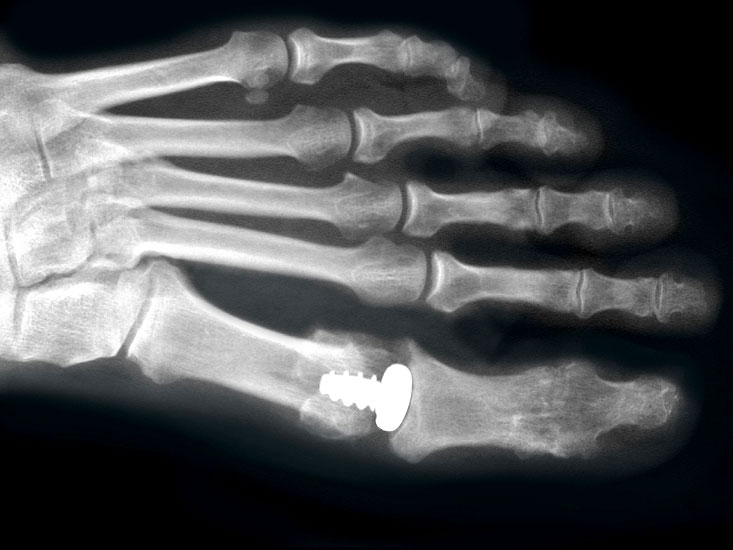

Resultate:

Die ersten Versuche mit der Prothetik am Großzehengrundgelenk wurden mit metallischen Hemi-Implantaten (Abb. 13, 14) vorgenommen. Eine Studie 47 mit größerem Kollektiv im Langzeitverlauf zeigte befriedigende Resultate, trotzdem hat sich die Technik bis heute nicht wirklich durchgesetzt. Der gleiche Autor verglich die Endoprothese mit der periartikulären Osteotomie und konnte keine wesentlichen Unterschiede feststellen 48. Eine neuere Studie vergleicht die Hemiarthroplastik mit der Arthrodese und der Resektionsarthroplastik und kann keine signifikanten Unterschiede feststellen 49. Metall–Polyäthylen-Paarungen zeigten eine hohe Lockerungsrate der Komponenten, weshalb sich diese Paarung ebenfalls nicht durchsetzte 505152. Am meisten Erfahrung besteht mit der Silikonprothese. Initial als Hemiprothese propagiert 46, wurde wegen mangelhaften Erfolgen 5354 die Totalprothese mit zwei Schäften eingeführt 55. Die Langzeitergebnisse sind widersprüchlich 55565758 so dass wegen der Verunsicherung dieses Model aktuell nicht regelmässig zum Einsatz kommt.